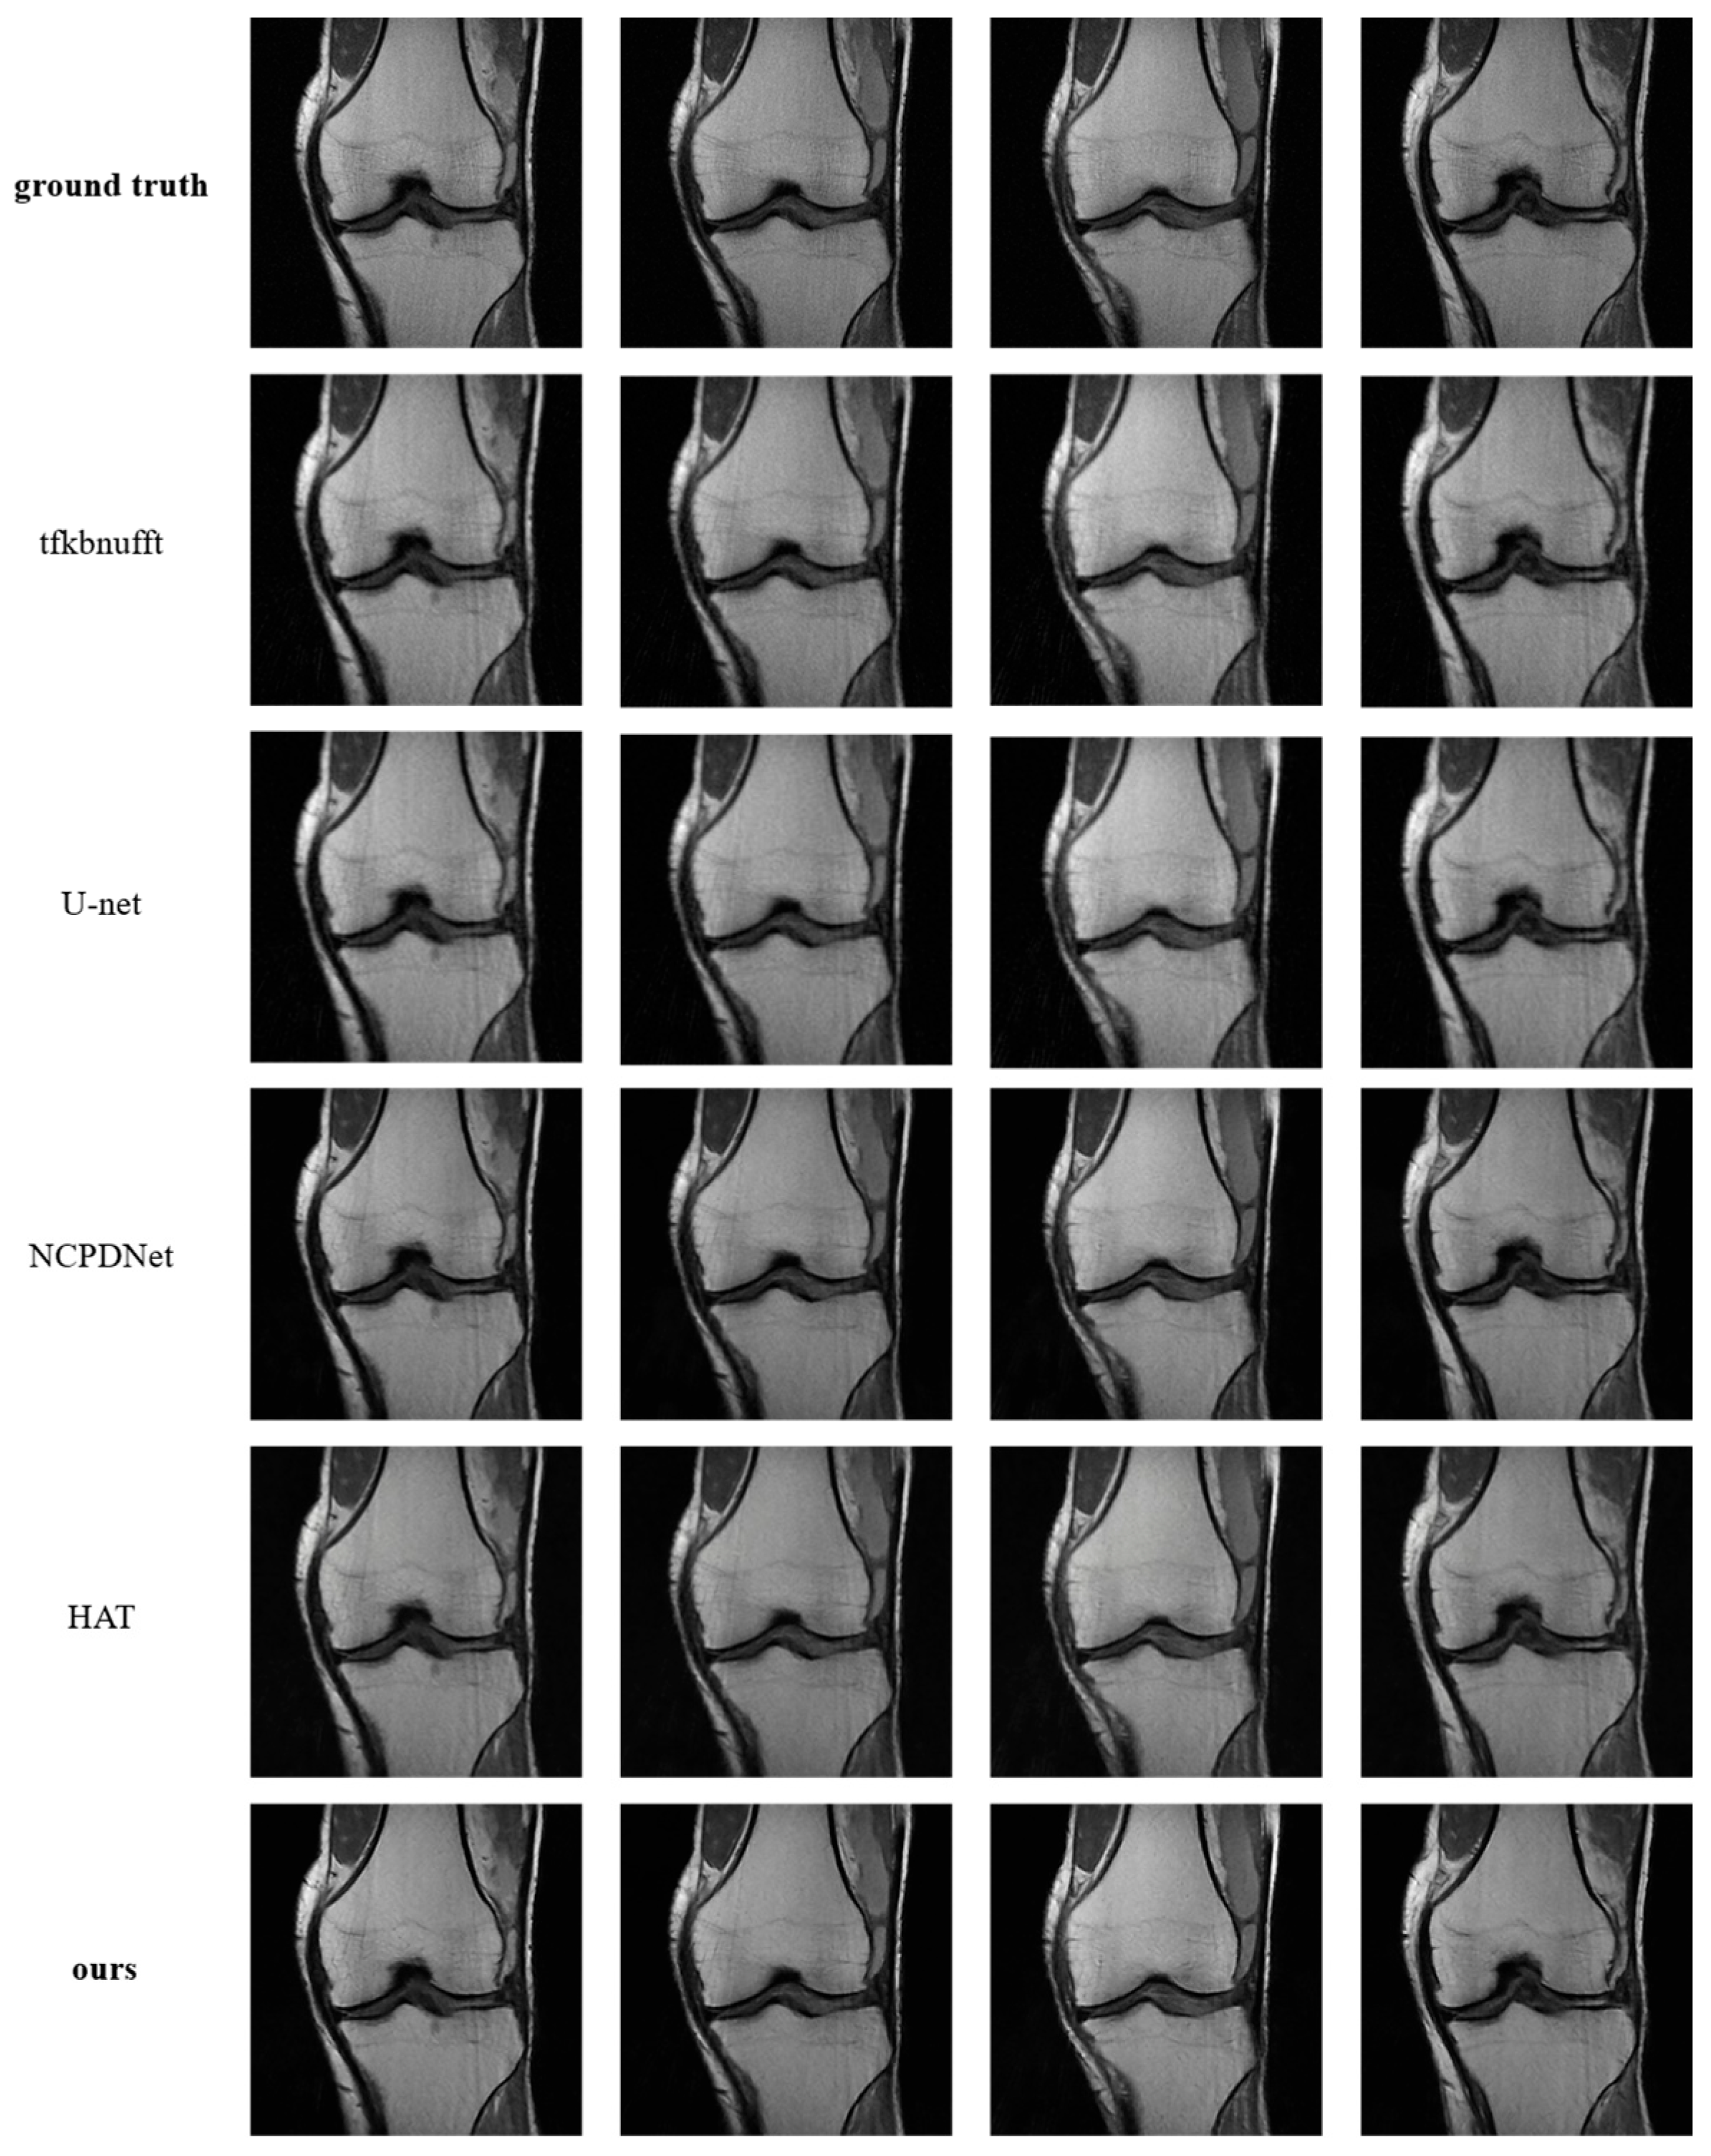

4.2.3. Contrast Experiment